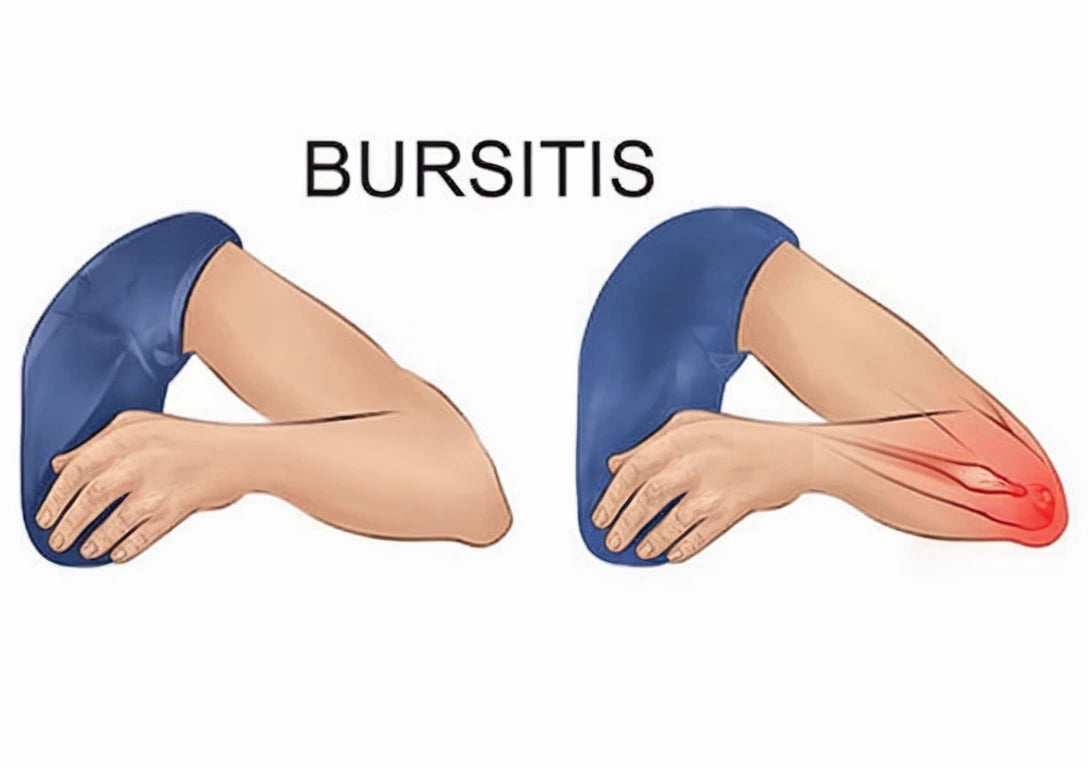

Armbågssmärta kan komma smygande eller plötsligt – särskilt vid upprepade rörelser eller belastning. Tennisarmbåge, musarm och inflammation är vanliga orsaker. I våra guider får du veta mer om diagnos och behandling.